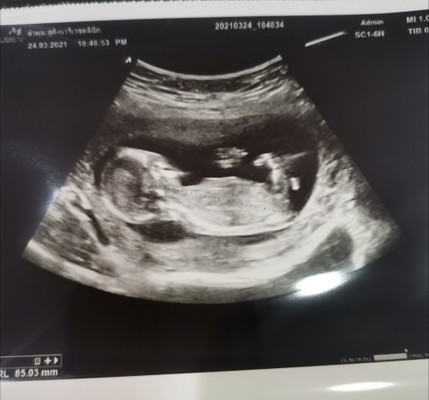

แม่ๆบ้านไหนทีมกันยาบ้างคะ บ้านนี้ได้14week2day มาแชร์ประสบการณ์กันหน่อยคะบ้านนี้ท้อง2แล้วยังตื่นเต้นเหมือนท้องแรกเลยคะ